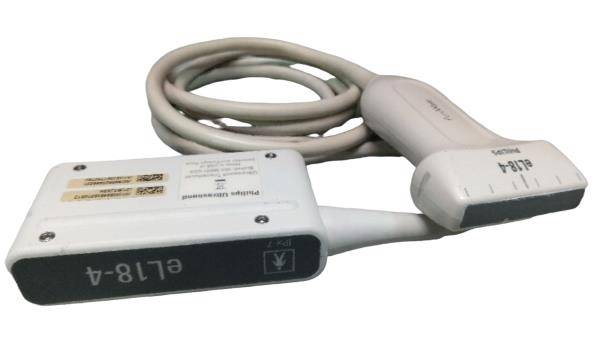

Probe: Convex + Linear + Micro convex heart 3 probes

The Laptop Ultrasound Scanner is an essential tool for healthcare professionals, as it combines Convex, Linear, and Micro Convex probes into one device. This versatility allows for a broad range of imaging applications, making it suitable for various medical settings. Whether you need to visualize abdominal organs or perform superficial assessments, this scanner meets and exceeds expectations. Because of its multiple probe options, medical practitioners can efficiently switch between different imaging modalities without the need for multiple devices.